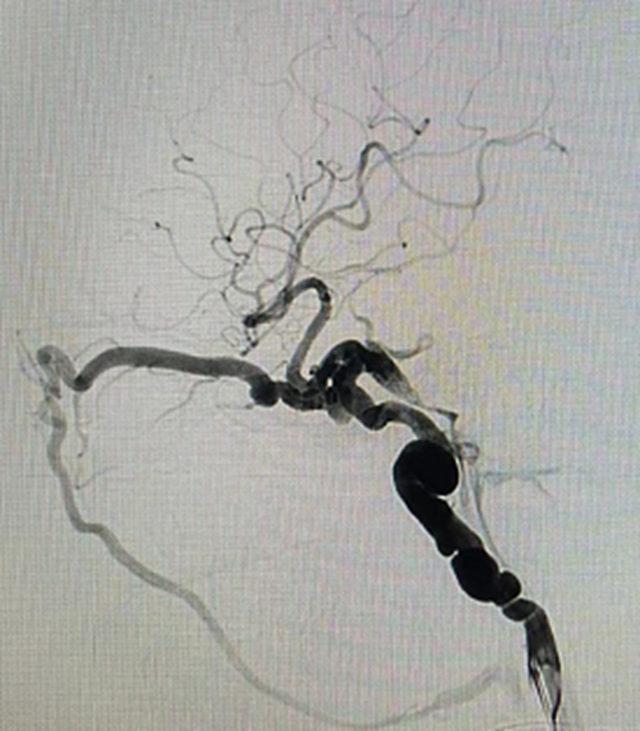

术前造影图片

考虑到患者病情迅速进行性加重的特殊性,在请示医院及科室领导后,黄昌仁教授带领团队根据疫情防控要求完善了相关术前准备,急诊在局部麻醉下,医生们先使用三维造影找到瘘口和引流静脉。随后,使用微导丝导引微导管进入眼静脉和岩下窦共同瘘口处,利用弹簧圈栓塞共同瘘口,再在球囊辅助下,使用胶水彻底栓塞颈动脉侧瘘口。栓塞后,工作角度造影显示瘘口消失,颈动脉通畅;栓塞后正侧位造影显示瘘口完全消失,大脑前动脉恢复血流,异常引流静脉消失。